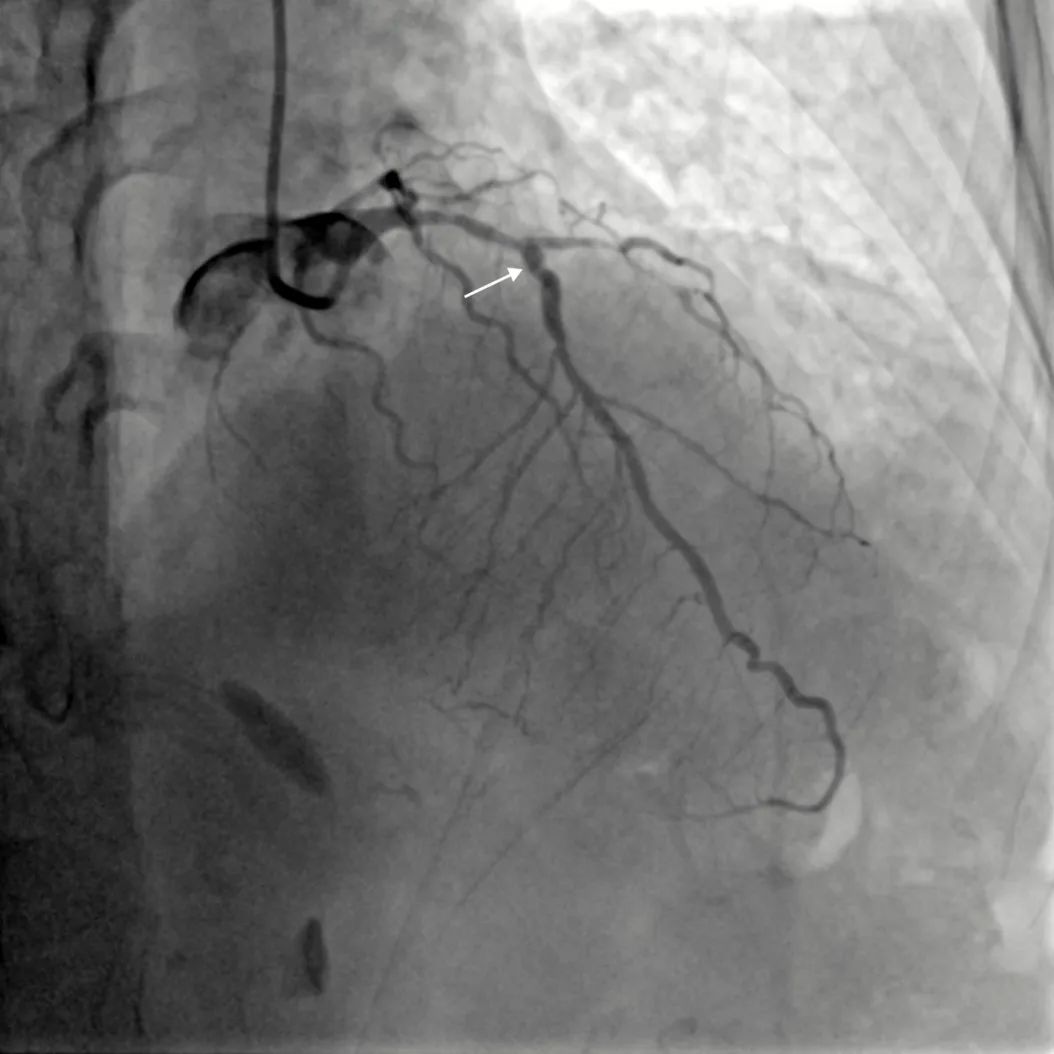

患者女,71岁,因“反复胸痛、胸闷4年余,加重”入院。患者入院诊断:冠心病不稳定心绞痛。入院完善相关检查后,患者2022年7月22日行冠脉造影提示:左主干无狭窄,前降支近段至中段90%狭窄伴钙化;回旋支近-中段弥漫性狭窄约70-90%;右冠近段至中段弥漫性狭窄约60-80%。拟对冠脉三支严重病变进行介入治疗。前降支近端至中段重度狭窄伴明显钙化。在使用2.5*15mm高压球囊,2.5*15mm切割球囊8-16atm反复预扩张后,仍无法充分扩张病变,考虑到前降支最重钙化病变处呈“小波浪”迂曲,行钙化病变旋磨术并发症风险较大,决定先完成左回旋支、右冠脉介入治疗后,择期再次对前降支严重钙化狭窄行介入治疗。

前降支造影:严重钙化狭窄病变处呈“小波浪”迂曲

前降支近段反复以高压球囊、切割球囊预扩张无法充分膨胀